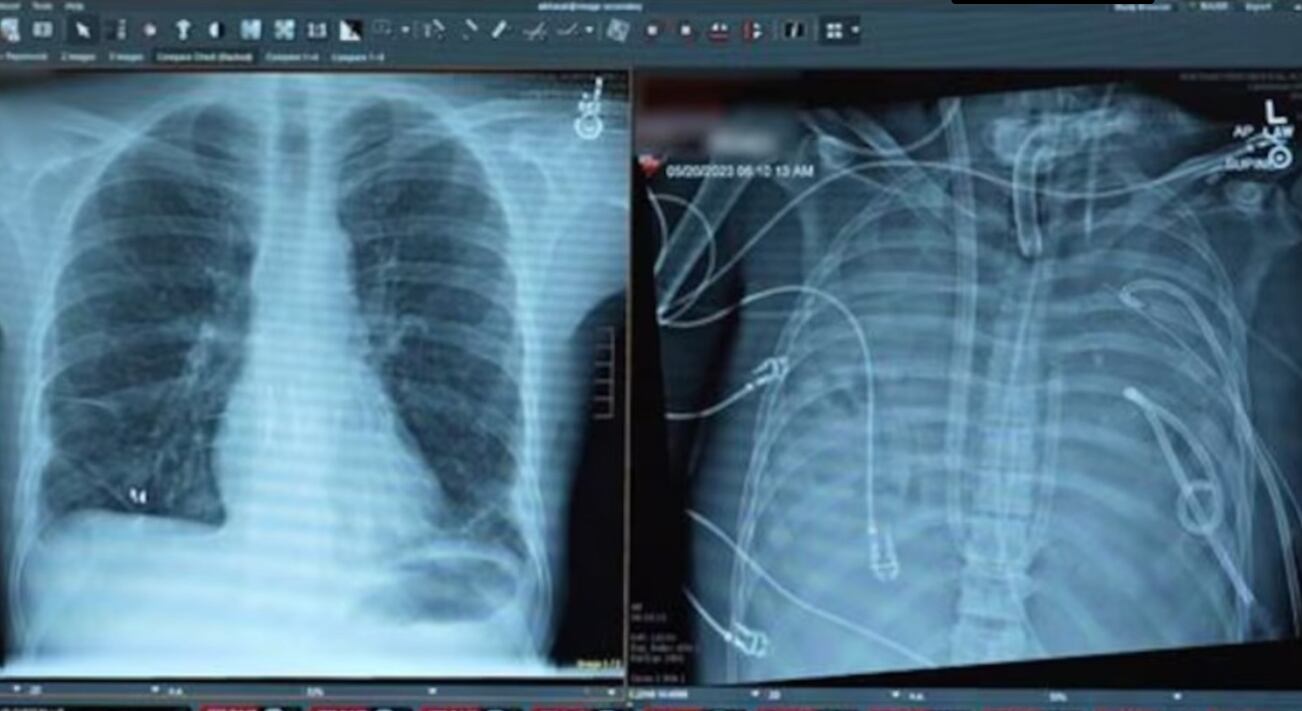

Pese al uso de ventilación mecánica y del sistema ECMO (oxigenación por membrana extracorpórea), el paciente continuó empeorando. Ante este escenario, los médicos tomaron una decisión extrema: extirpar completamente los pulmones infectados para eliminar el foco de la sepsis.

El mayor desafío era mantener con vida al paciente sin pulmones. Para ello, el equipo diseñó un sistema pulmonar artificial extracorpóreo capaz de oxigenar la sangre, eliminar el dióxido de carbono y mantener un flujo sanguíneo estable.

El dispositivo permitió estabilizar la presión arterial, evitar el colapso cardíaco y recuperar la función de otros órganos, mientras la infección disminuía progresivamente.

Gracias a este soporte artificial, el paciente se mantuvo con vida durante dos días sin pulmones, hasta que se consiguió un donante compatible. Entonces, los médicos realizaron con éxito un trasplante doble de pulmón.